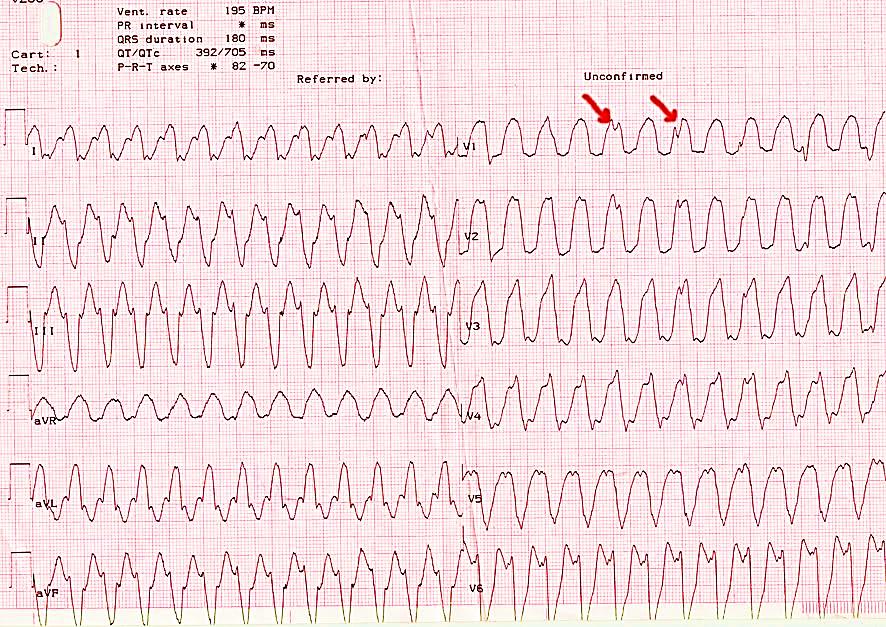

Желудочковая пароксизмальная тахикардия (рис. 27)

• Внезапно начинающийся и так же внезапно заканчивающийся приступ учащения сердечных сокращений до 140-220 в минуту при сохранении в большинстве случаев правильного ритмаю

• Деформация и расширение комплекса QRS более 0,12 с дискордантным расположением сегмента RS-T и зубца T.

• АВ-диссоциация, т.е. полное разобщение частого ритма желудочков (комплексы QRS) и нормального ритма предсердий (зубцы Р) с изредка регистрирующимися одиночными нормальными неизмененными комплексами QRST синусового происхождения ("захваченные" сокращения желудочков) (рис. 28)

Рис. 27. Желудочковая тахикардия